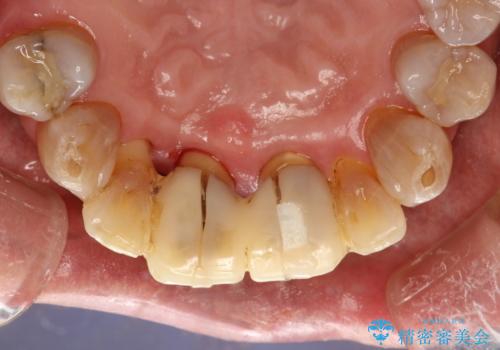

歯周外科前のクリーニング

- 歯周外科を行う前に、しっかりと汚れを除去し外科治療がスムーズに行えるようにとのことでPMTC30分コースを行いました。

治療前のクリーニングを行うことで、より処置がスムーズに行えること・処置後の腫れや感染予防にもなります。また、外科治療をおこなった後は、傷口の治りを待つため、しっかりとブラッシングできない状態になります。そのため処置前に、なるべくお口の中を清潔にしておくことが大切です。